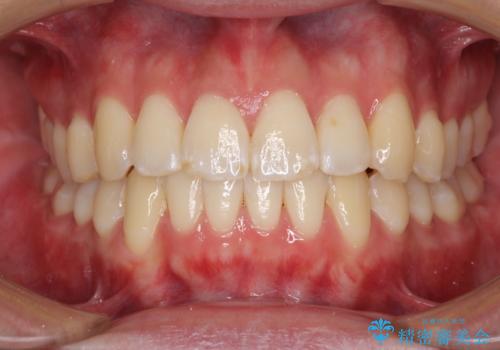

全顎的なクロスバイト 補助装置を用いてワイヤー矯正

- 八重歯や奥歯の噛みにくさを気にして来院された患者様です。

前歯のクロスバイトや八重歯の他に、左右最後臼歯のシザーズバイト(鋏状咬合)が認められました。

シザーズバイト改善のために補助装置を使用しながら、ワイヤー装置にて全体の歯列を整えることとしました。